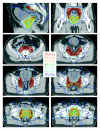

Methods: For ten patients with localized prostate cancer, IMRT plans with a simultaneous integrated boost (SIB) were generated for treatment of the prostate only (plan-PO) and for additional treatment of the pelvic lymph nodes (plan-WP). In plan-PO, doses of 60 Gy and 74 Gy (33 fractions) were prescribed to the seminal vesicles and to the prostate, respectively. Three plans-WP were generated with prescription doses of 46 Gy, 50.4 Gy and 54 Gy to the pelvic target volume; doses to the prostate and seminal vesicles were identical to plan-PO. The risk of rectal, bladder and small bowel toxicity was estimated based on NTCP calculations.

Results: Doses to the prostate were not significantly different between plan-PO and plan-WP and doses to the pelvic lymph nodes were as planned. Plan-WP resulted in increased doses to the rectum in the low-dose region </= 30 Gy, only, no difference was observed in the mid and high-dose region. Normal tissue complication probability (NTCP) for late rectal toxicity ranged between 5% and 8% with no significant difference between plan-PO and plan-WP. NTCP for late bladder toxicity was less than 1% for both plan-PO and plan-WP. The risk of small bowel toxicity was moderately increased for plan-WP.